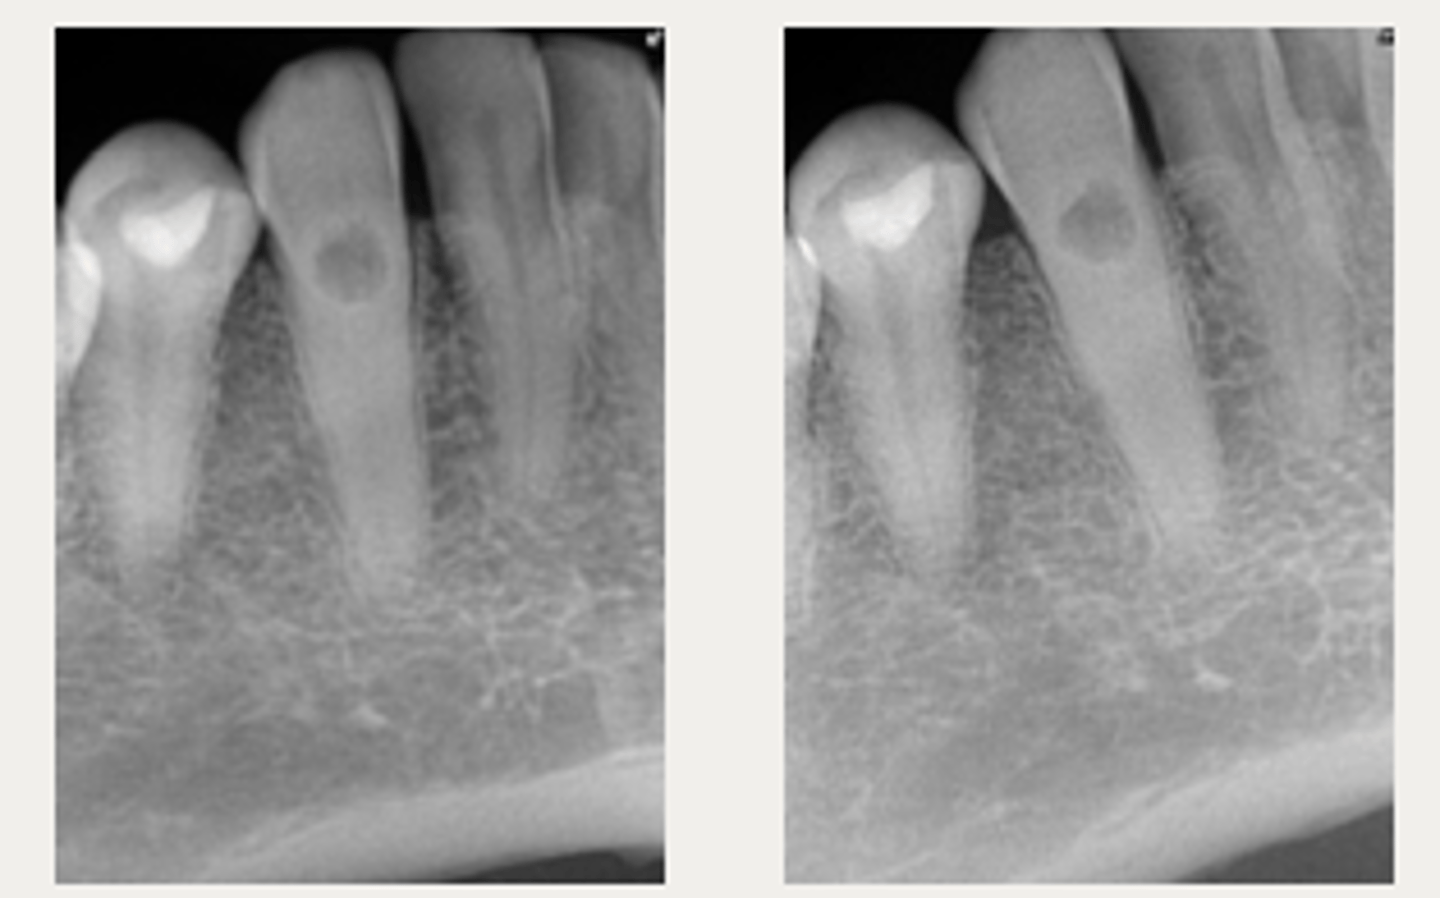

External Inflammatory Resorption (EIR)

Which type of resorption?

Lateral External Inflammatory Resorption

ID the type of resorption:

CLINICAL:

- History of trauma

- Pulpal Dx → necrotic

- Symptoms of apical periodontitis

- - May be tender to percussion and/or palpation

RADIOGRAPHIC:

- Radiolucent, crater shaped indentations on the root surface with adjacent bone loss and periradicular radiolucencies

Patient presents with history of trauma, does not respond to sensibility tests (necrotic pulp), is tender to percussion and/or palpation and has these radiographic findings. What is the most likely diagnosis?